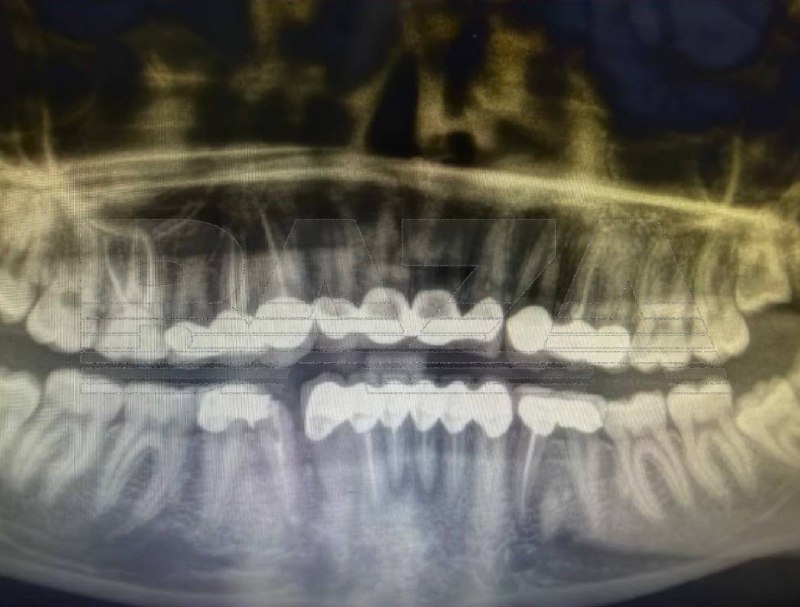

Россиянка полетела в Турцию за «улыбкой как у Егора Крида», но получила воспаление и сломанные коронки, — СМИ.

Девушка поехала в турецкую клинику ставить виниры, однако во время процедуры ей сильно

спилили зубы и фактически установили

коронки и мосты. После лечения начались сильные боли и в клинике ей

удалили шесть нервов.Позже воспаление вернулось — в экстренной стоматологии врачи

обнаружили инфекцию, удалили ещё несколько нервов и предупредили о риске госпитализации. Одна из коронок также треснула, а новое лечение оценивают примерно в